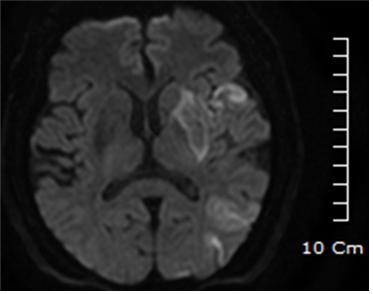

사진1. 69세 남성 환자. 사진 상 오른쪽의 하얗게 밝은 부위가 언어 중추에 생긴 뇌경색